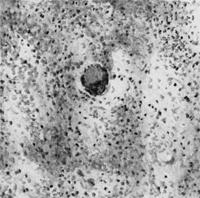

Бруцеллы проникают в организм через кожу или слизистые оболочки, захватываются иммунными клетками тканей, размножаются в них и током лимфы заносятся в регионарные лимфатические узлы, а из последних по лимфатическим и кровеносным сосудам распространяются по всему организму. Схема развития бруцеллеза включает пять фаз течения инфекции: лимфогенную; гематогенную; фазу полиочаговых локализаций; фазу экзоочаговых обсеменений; фазу метаморфоза. Степень …